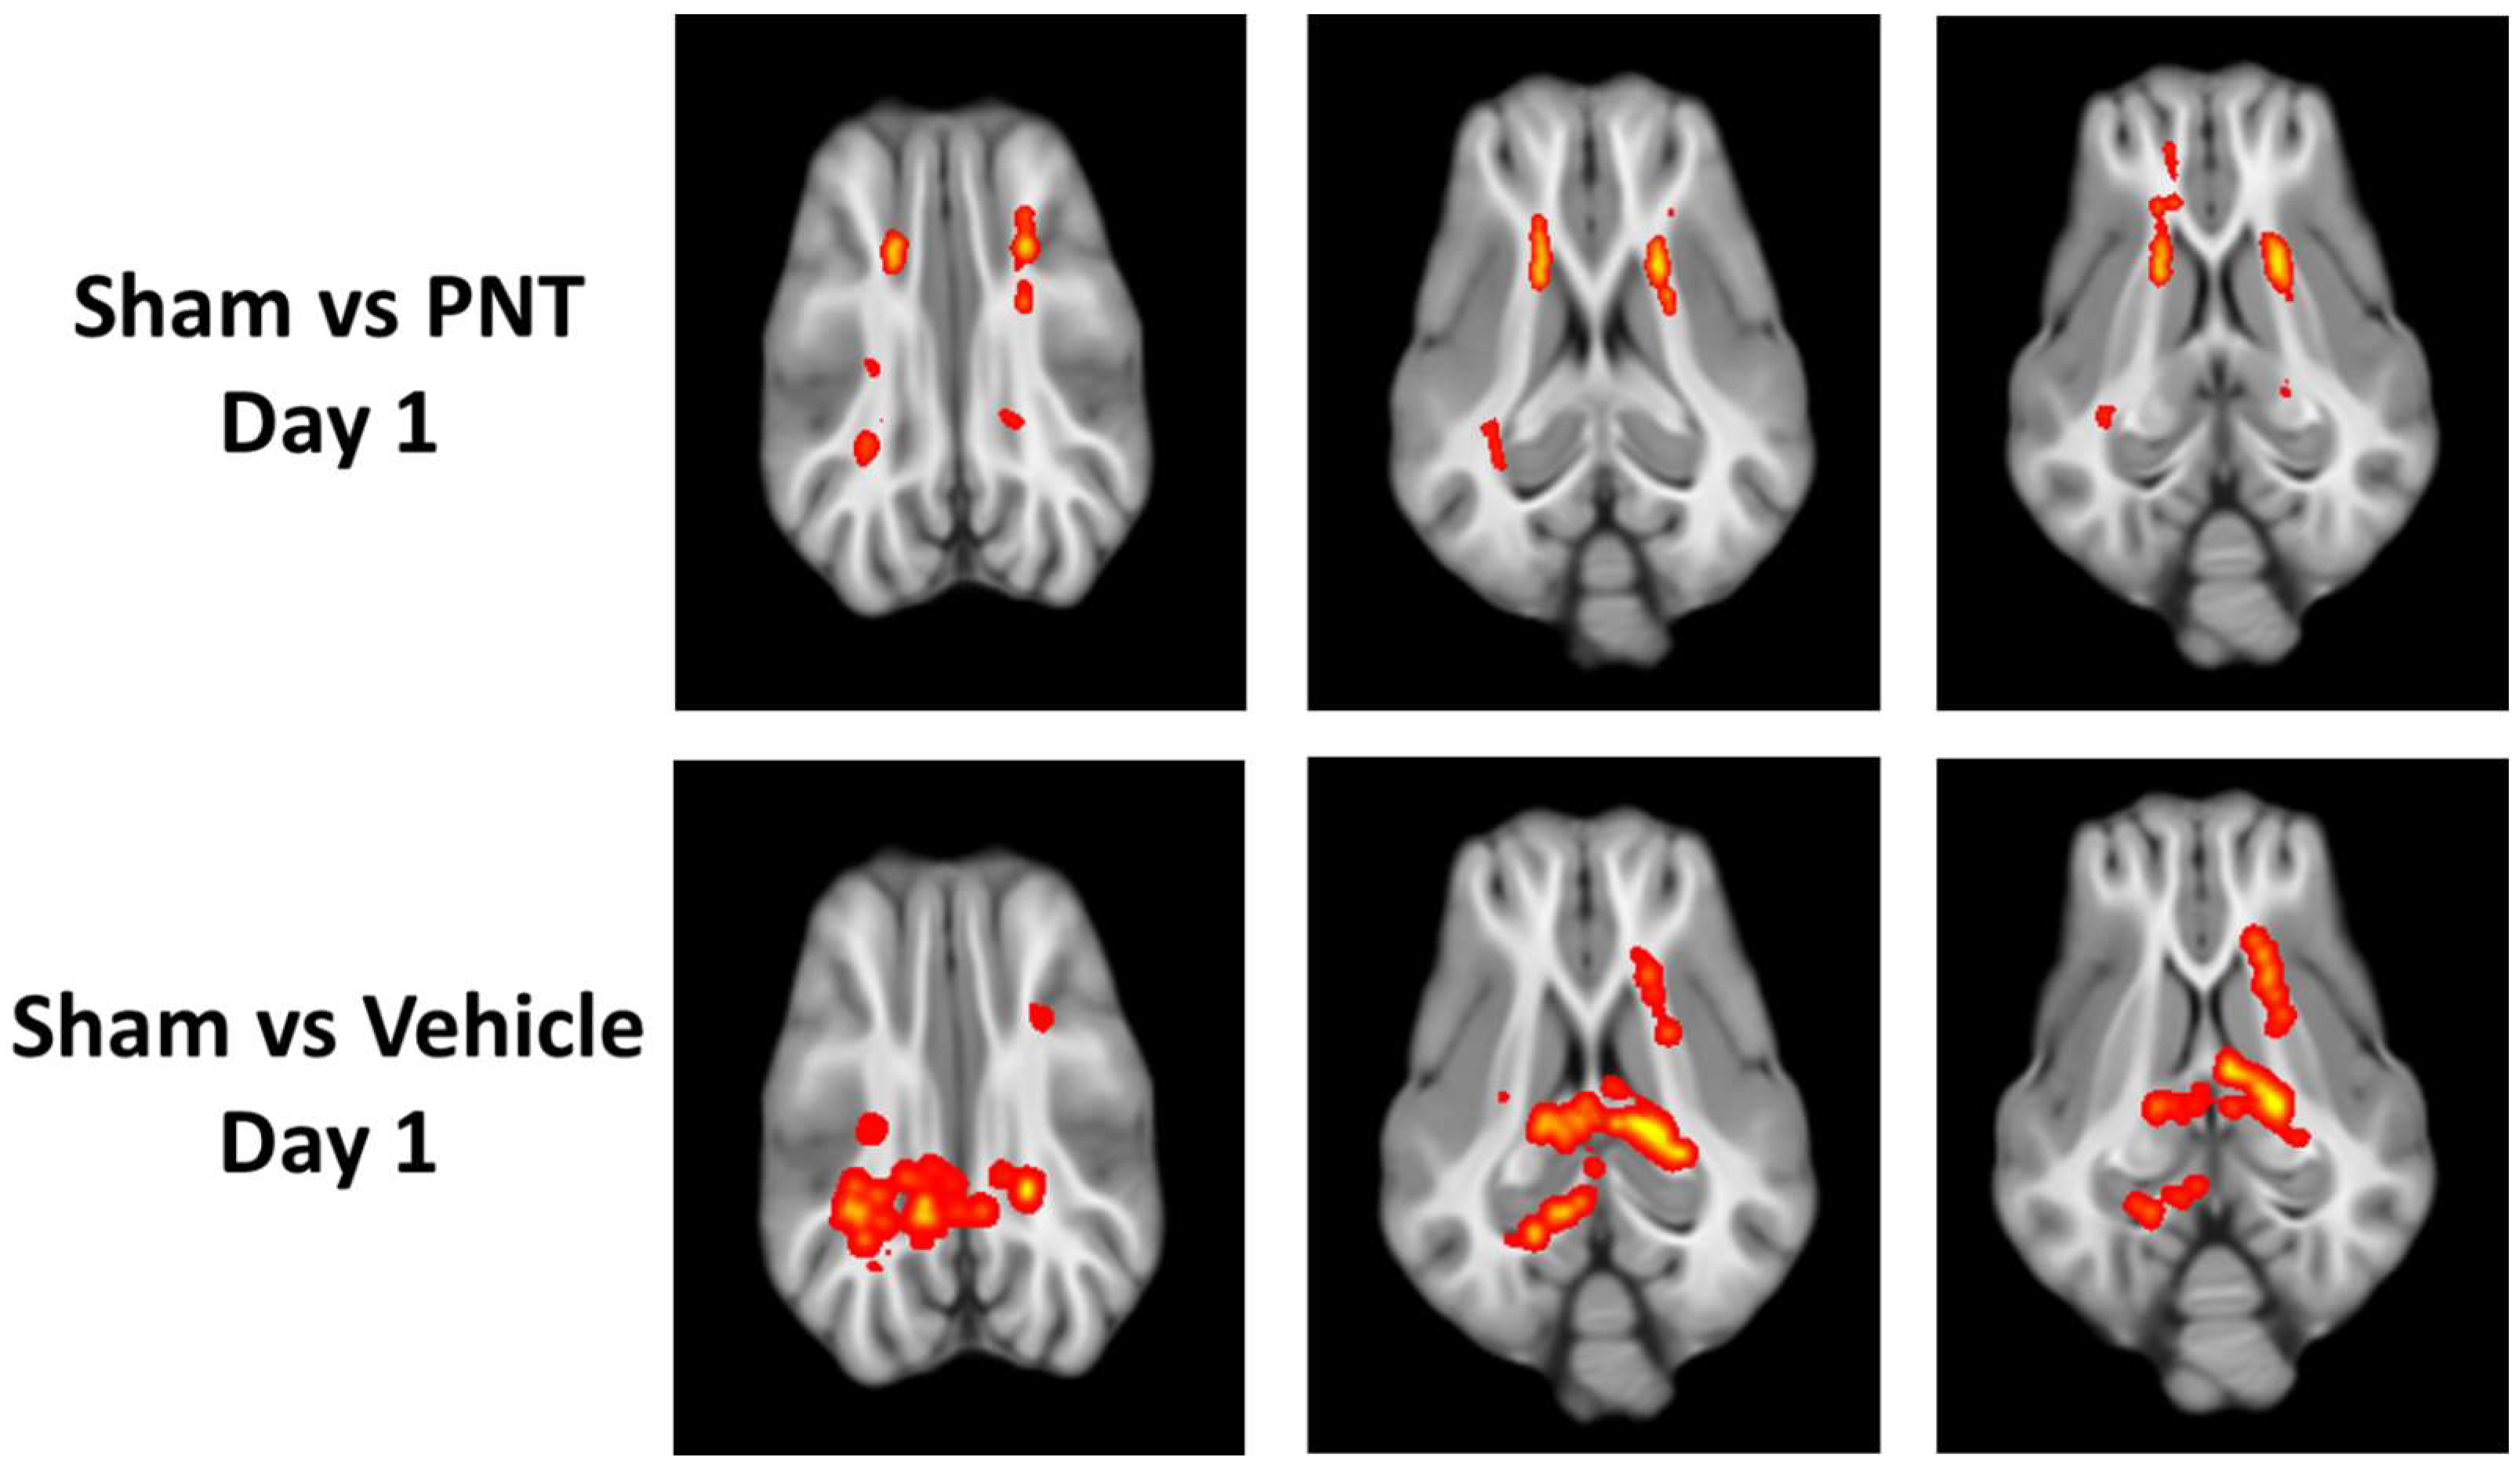

After the administration of the vehicle or PNT001(60 mg/kg, intravenous), we analyzed drug exposure in an initial subset of eight animals in both serum and CSF to validate the appropriate administration (Figure S1). This showed the appropriate drug levels in the serum and CSF of the pigs, which were in agreement with the previously demonstrated Kd of PNT [10]. Then, we analyzed the time course of white matter integrity using DTI at 1 day and 14 days. At 1 day following TBI, there were multiple areas of significant reduction in FA among both the PNT001- and vehicle-treated CCI pigs (Figure 2). Both the PNT001-treated and vehicle-treated injured animals exhibited reduced FA levels in the corona radiata. Whereas the PNT001-treated animals appeared to have smaller areas of FA reduction in the bilateral corona radiata, the vehicle-treated group appeared to have larger areas of FA reduction. Specifically, the contralateral (left) corona radiata and posterior portion of the corpus callosum showed an FA reduction.

For the quantification of the white matter integrity, we normalized the FA values to our historical sham animals’ FA levels in each respective area, as shown in (Figure 3). In agreement with the heat map of the areas with FA reduction (Figure 2), there was a significant decrease in the FA values of the corona radiata for both the vehicle- and PNT001-treated groups compared to the sham pigs. The PNT001-treated pigs also displayed a reduction in the MD in the corpus callosum, while the vehicle-treated group did not. When DTI was performed again at the 14-day time point (Figure 4), there were significant reductions in the areas in which FA decreases were acutely observed. The quantification of the reductions in the FA in these regions at 14 days resulted in significant differences between the sham and vehicle groups but not the sham and PNT001 groups at the right corona radiata (Figure 5). Although the heat map showed small areas of FA reduction in the bilateral corona radiata, because the region of FA reduction was very small, the quantitative assessment showed no significant difference between the sham and vehicle or PNT001 groups in the left corona radiata. Similarly, the longitudinal study using linear mixed effects model showed no significant differences between the two groups for FA and MD (Table S1).

In the DTI scans of pigs following TBI, specific areas of FA reduction were found in the bilateral corona radiata and splenium of the corpus callosum. These areas of injury were consistent with our previously reported DTI data on 30-day post-injury pigs [16], indicating the selective vulnerability of these regions to TBI. Changes in FA levels at the ipsilateral corona radiata were specifically correlated with rises in both NFL and GFAP also in this study, supporting the validity of these radiographical findings. Although the quantification of FA values at each location showed no significant differences between the vehicle-treated and PNT001-treated groups, the subtle differences in the size of the area with FA changes between the two groups was more clear in the heat maps. These data showed that while there was no major effect in reducing the white matter damage by PNT001, the subtle reduction, as shown by heat map, may indicate that optimal dose and administration times should be explored. Over the 14 days, the areas of FA reduction were significantly attenuated, as shown between Figure 2 and Figure 4. This change may be partly due to the recovery process of white matter injury over time, but decreasing tissue edema may also account for this, as previously noted [16].

Figure 2. FA map showing difference between sham vs PNT-treated CCI group (top) and sham vs vehicle-treated CCI group (bottom) at 1 day following injury. The red–yellow regions show FA-reduced areas as compared to sham group.